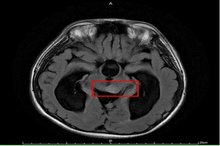

【新唐人亞太台 2020 年 09 月 23 日訊】15歲男孩因頭痛不適昏倒,被家人緊急送醫,經急診診斷疑為水腦合併癲癇,施以抗癲癇藥物治療。但男孩父母對癲癇病情仍有疑慮,故帶至臺大醫院新竹分院小兒神經科門診就醫。透過檢查,發現男孩眼動受限,眼睛無法往上看及往外側注視,醫師問診發現,他自小學四年級就開始頭痛,且因眼動受限而時常跌倒。經腦部核磁共振檢查確診為水腦併中腦腫瘤,立即安排手術治療。

臺大醫院新竹分院小兒部小兒神經科張寶玲醫師表示,在臨床經驗中,頭痛是病童最常抱怨的問題,尤其是小學高年級及國、高中學童;其中大部分為原發性頭痛,如偏頭痛及緊縮型頭痛等。然而,如小朋友有日漸增強或頻率增加之頭痛,且併有不對稱之神經學異常,如:單側肢體無力、抽搐、眼動異常、步態不穩或有全身性症狀,如:發燒或體重下降等,應注意有可能是「繼發性頭痛」,也就是明確病因所引起之頭痛,如:感染或腫瘤所致,提醒民眾應立即就醫治療。